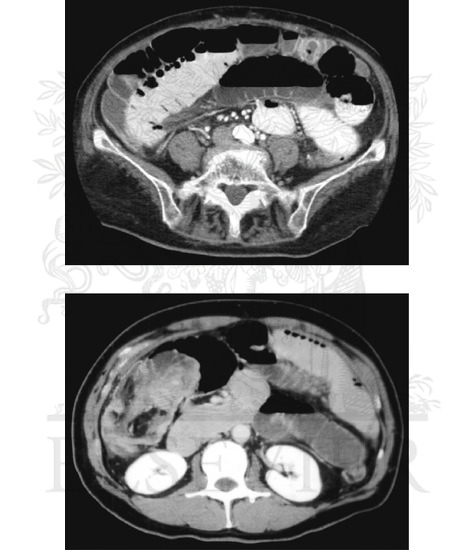

Intestinal Obstruction (Continued): Computed Tomography of Small Intestine Obstruction